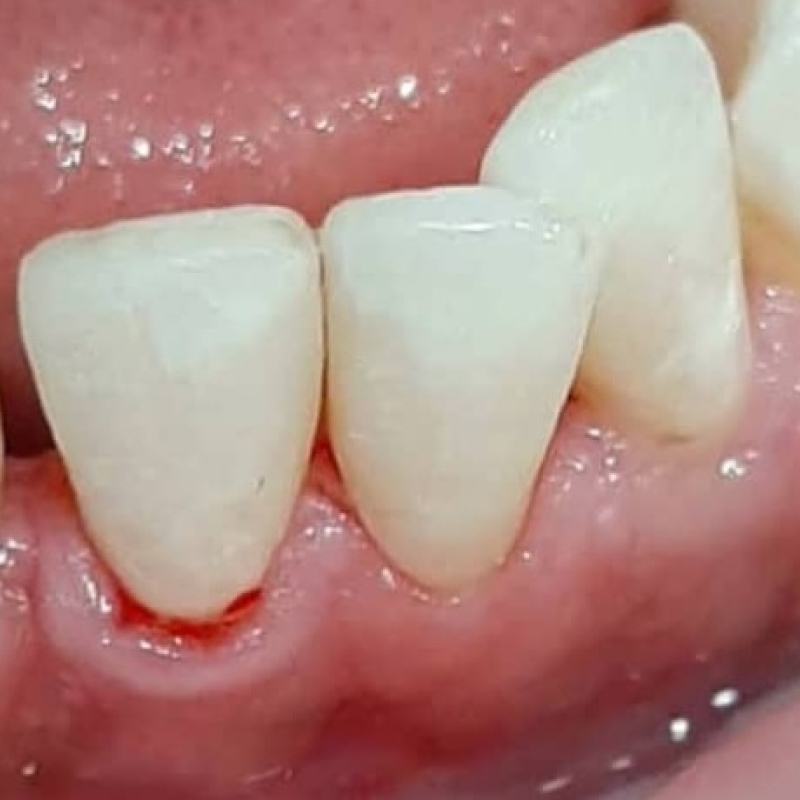

Устранение хронического апикального периодонтита зуба 1.7 с временным восстановлением коронкиСмотреть работуСрок лечения:2 визитаСумма лечения:14 337 руб.